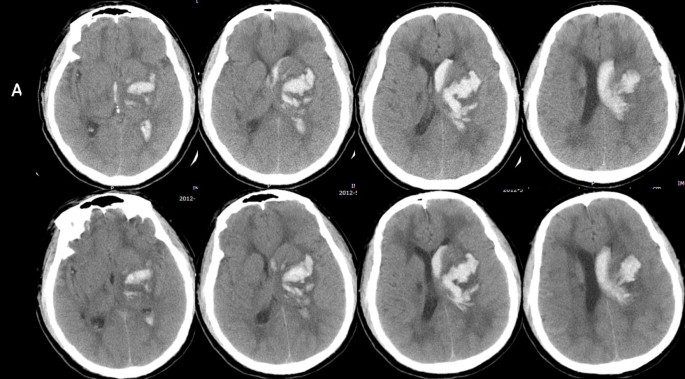

Хроническая ишемия головного мозга и лейкоареоз: симптомы и лечение